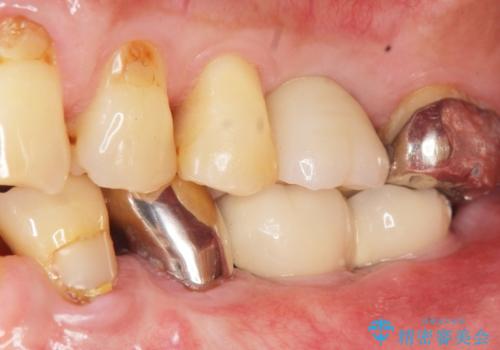

奥歯のインプラント ソケットリフト 60代男性

- 奥歯のインプラントをご希望し、来院された患者様です。

精査したところ上顎骨の厚みが薄かったため、ソケットリフト(上顎洞底挙上術)を併用してインプラント治療を行いました。